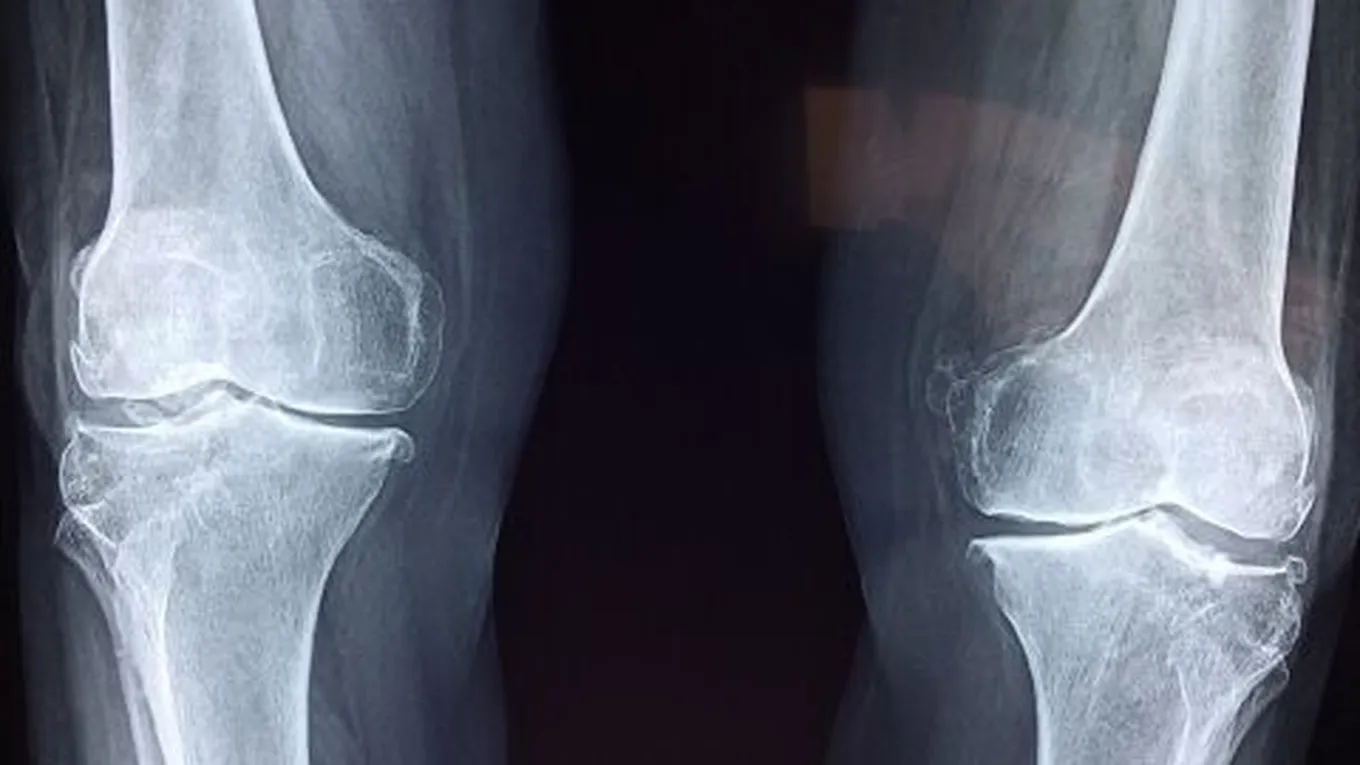

أفضل علاج لخشونة المفاصل

العلاجات المنزليةهناك العديد من العلاجات المنزليّة المختلفة التي تخفف من مشكلة خشونة المفاصل، أو ما يُعرَف بالفصال العظميّ (بالإنجليزية: Osteoarthritis)، وفيما

هناك العديد من العلاجات المنزليّة المختلفة التي تخفف من مشكلة خشونة المفاصل، أو ما يُعرَف بالفصال العظميّ (بالإنجليزية: Osteoarthritis)، وفيما يأتي بيان لبعض هذه العلاجات:[1]